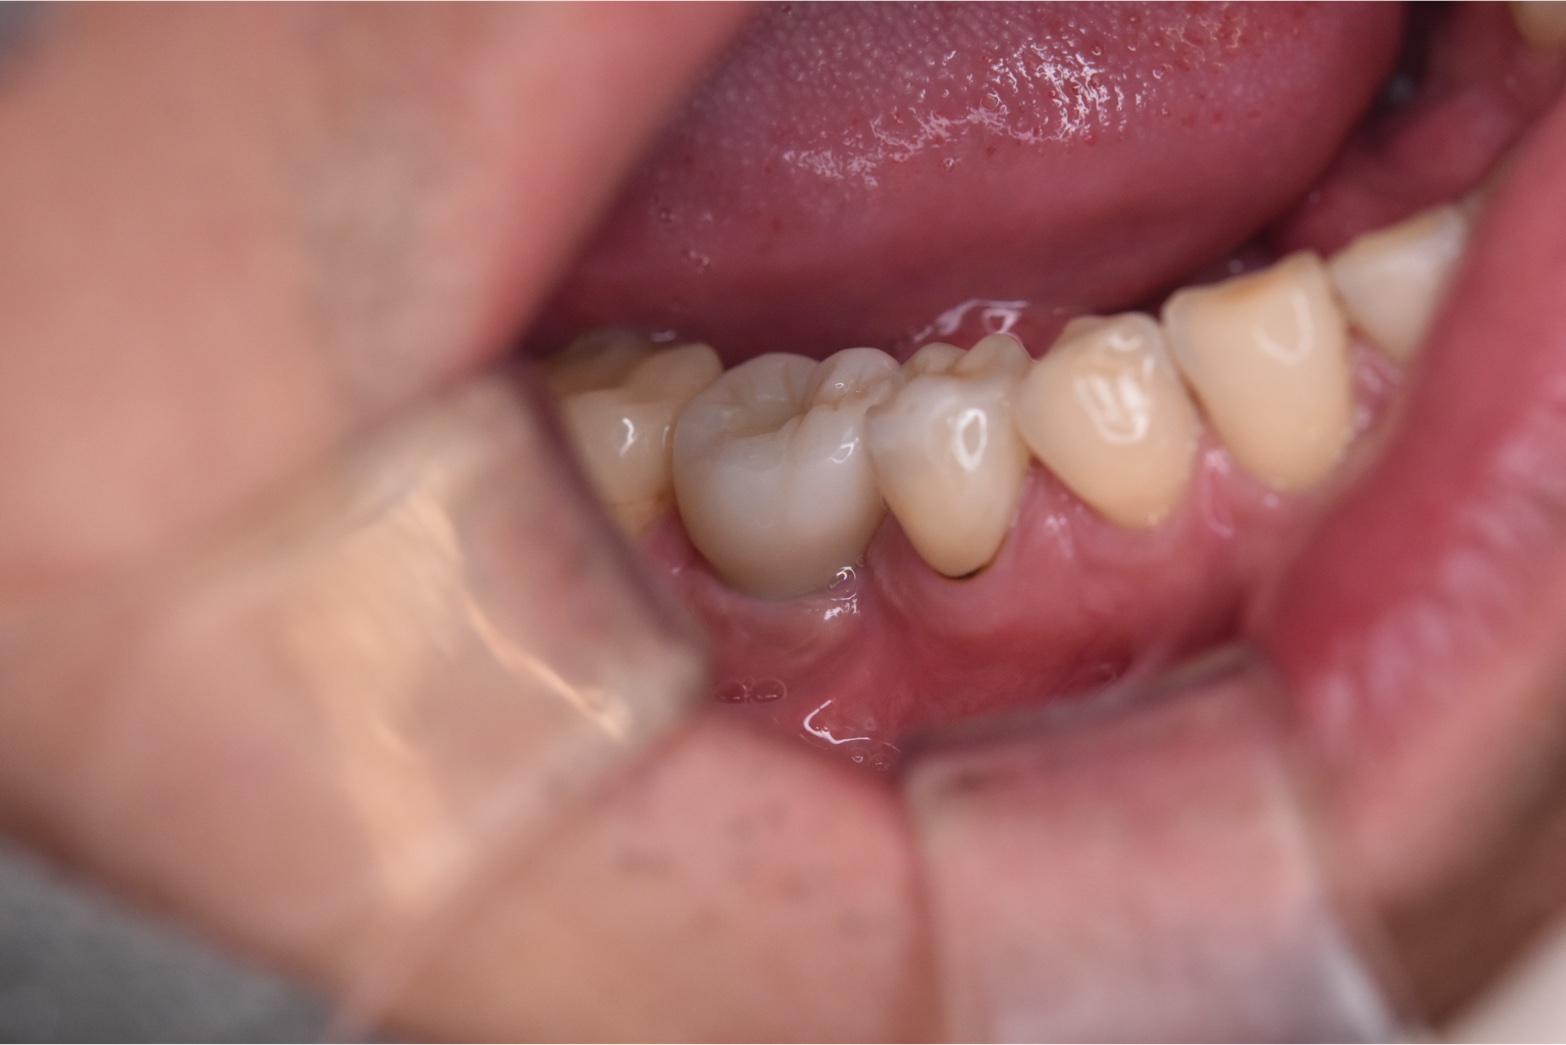

自然な見た目としっかりした噛み心地のインプラントを装着することができました。

40代のインプラント治療後の口腔内写真

After